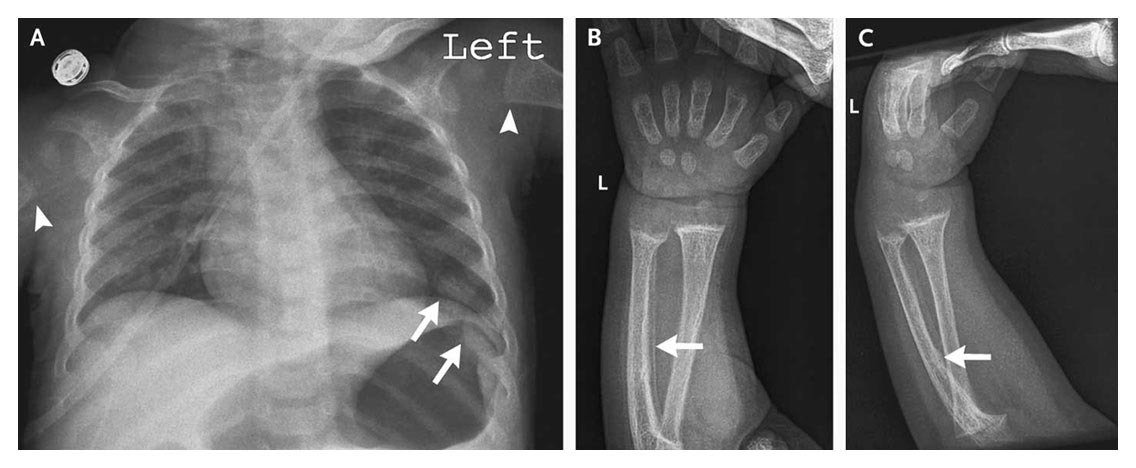

1) "Case 3-2009 — A 9-Month-Old Boy with Seizures" nejm.org/doi/full/10.10…